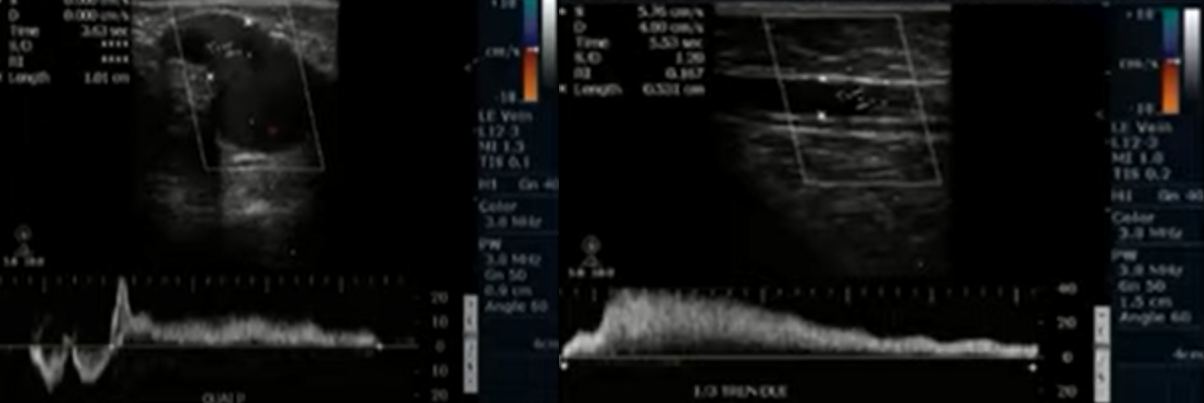

- Chẩn đoán xác định suy van tĩnh mạch:

- Dòng trào ngược tĩnh mạch tự nhiên hoặc khi làm các nghiệm pháp (Valsalva, bóp cơ) là dấu hiệu quan trọng nhất để chẩn đoán:

- Thời gian dòng trào ngược kéo dài trên 500ms với các tĩnh mạch nông và tĩnh mạch sâu vùng cẳng chân

- Thời gian dòng trào ngược kéo dài trên 1000ms với tĩnh mạch đùi và khoeo